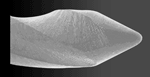

Non-cutting tip – Minimizes ledging and transportation (Fig. 1).

Fig. 1: K3 file non-cutting tip, SEM. Rake Angle – The K3 has a slightly positive angle that maximizes cutting efficiency (Fig. 2).